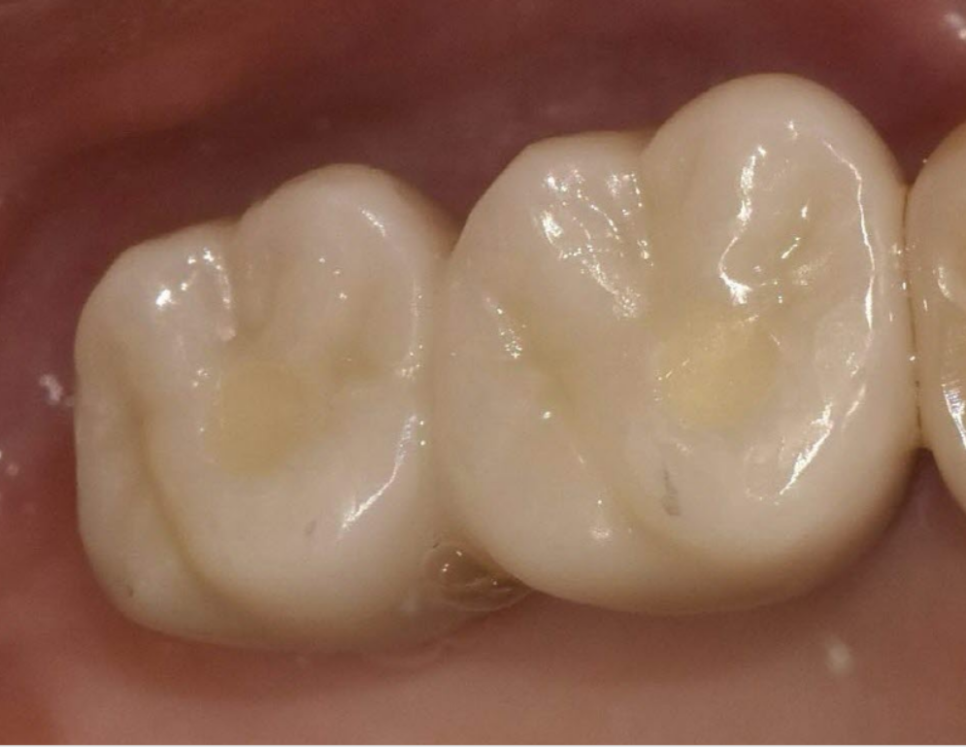

1개월 후 경과 확인

환자분의 강한 치료 의지와 저의 노력 덕분일까요?

250220

염증이 점차 가라앉으면서 치아가 안정되기 시작했습니다.

흔들림도 눈에 띄게 줄어들었습니다.

최종적으로 보철물(크라운)까지 씌워드렸고, 현재는 건강하게 사용하고 계십니다.

250220 치아 뿌리 염증 빼야 된다는 치아, 이렇게 살렸습니다. 치료 방법